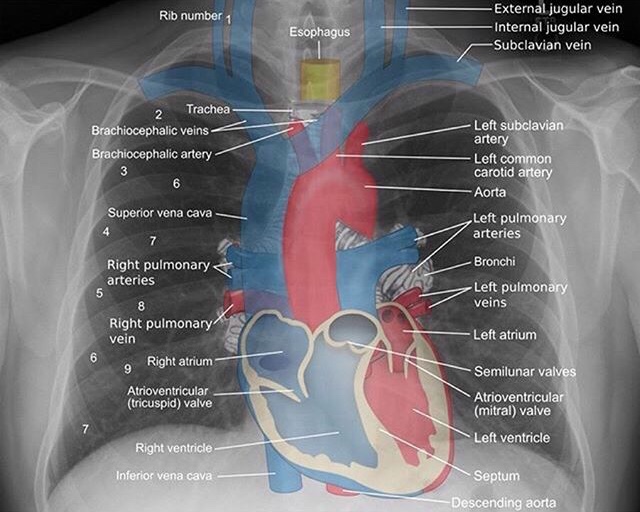

1) NORMAL CHEST XRAY

Airway: The trachea is located in the midline. Inspect the trachea and right and left main bronchi. If the trachea is pushed to the left or right look for a cause. Either mass effect pushing the trachea or volume loss (atelectasis) pulling on it.

Breathing: The lobes of the lungs. 3 on the right (upper, middle, lower) and two on the left (upper and lower). Look for consolidation, nodules, masses. Things replacing normal aerated lung (black) will show up as white.

Cardiac: look at the heart size (should be less than 50% of the diameter of the chest). Make sure the borders are clear and sharp. The right atrium makes up the right heart border and the left ventricle makes up the left heart border on the chest X-ray. If the border is obscured, think pneumonia or mass.

Diaphragm: should be well defined to the costophrenic angle. Becomes obscured by lower lobe pneumonia and pleural effusions. Always look for free air under the diaphragm.

Everything else:

- Bones – look for fractures and destructive lesions

- Hilar contours – look for enlargement caused by lymphadenopathy or masses

- Vascular structures – enlarged pulmonary arteries and aortic aneurysms.